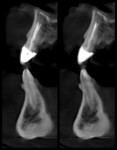

A 38-year-old male patient presented with a maxillary left central incisor that was "loose." He reported that when he was younger, he suffered an accident that lead to multiple teeth being broken, including both of his maxillary central incisors, which required endodontic treatment and were restored with PFM crowns. The patient explained that, recently, he was eating when his tooth suddenly felt like it became loose. Upon examination, tooth No. 9 exhibited significant clinical mobility, so a cone-beam computed tomography (CBCT) scan was performed. After reviewing the images, a horizontal root fracture was noted (Figure 1), and the tooth was deemed non-restorable. At that time, the pros and cons of restoration with a dental implant versus a fixed partial bridge were discussed with the patient. Preoperative photos were taken (Figure 2 through Figure 6), and a full clinical examination was completed. It was also noted that the patient demonstrated significant crowding among his lower anterior teeth as well as significant pathway wear and a deep bite-all of which contributed to the fracture of tooth No. 9 (Figure 5 and Figure 6). After a detailed workup, the patient was referred to an orthodontist for evaluation and possible treatment. He was presented with a comprehensive treatment plan that included correcting his overall bite and tooth position; however, he declined all longer-term treatment modalities, requesting only that his front tooth be replaced with a dental implant and that he receive a fixed provisional restoration as opposed to a removable partial denture. After a discussion, the decision was made to replace the crown on tooth No. 8 at the time that tooth No. 9 was extracted and replaced with an implant so that tooth No. 8 could be used to cantilever a fixed partial temporary restoration at the No. 9 site.